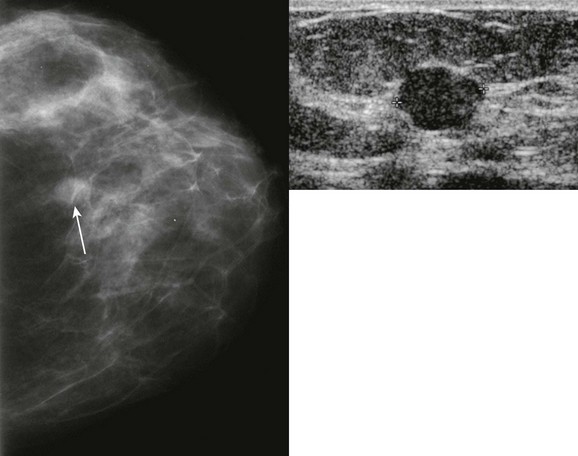

FIGURE 11-2 ILC.

A 49-year-old woman with a firm palpable lump in the right breast. Mammogram is normal in the palpable area that is marked by a triangle. US shows multiple hypoechoic areas with shadowing but no discrete mass, which is characteristic of ILC. (Reprinted with permission from Harvey JA. Unusual breast cancers: Useful clues to expanding the differential diagnosis. Radiology 2007;242:683-694.)